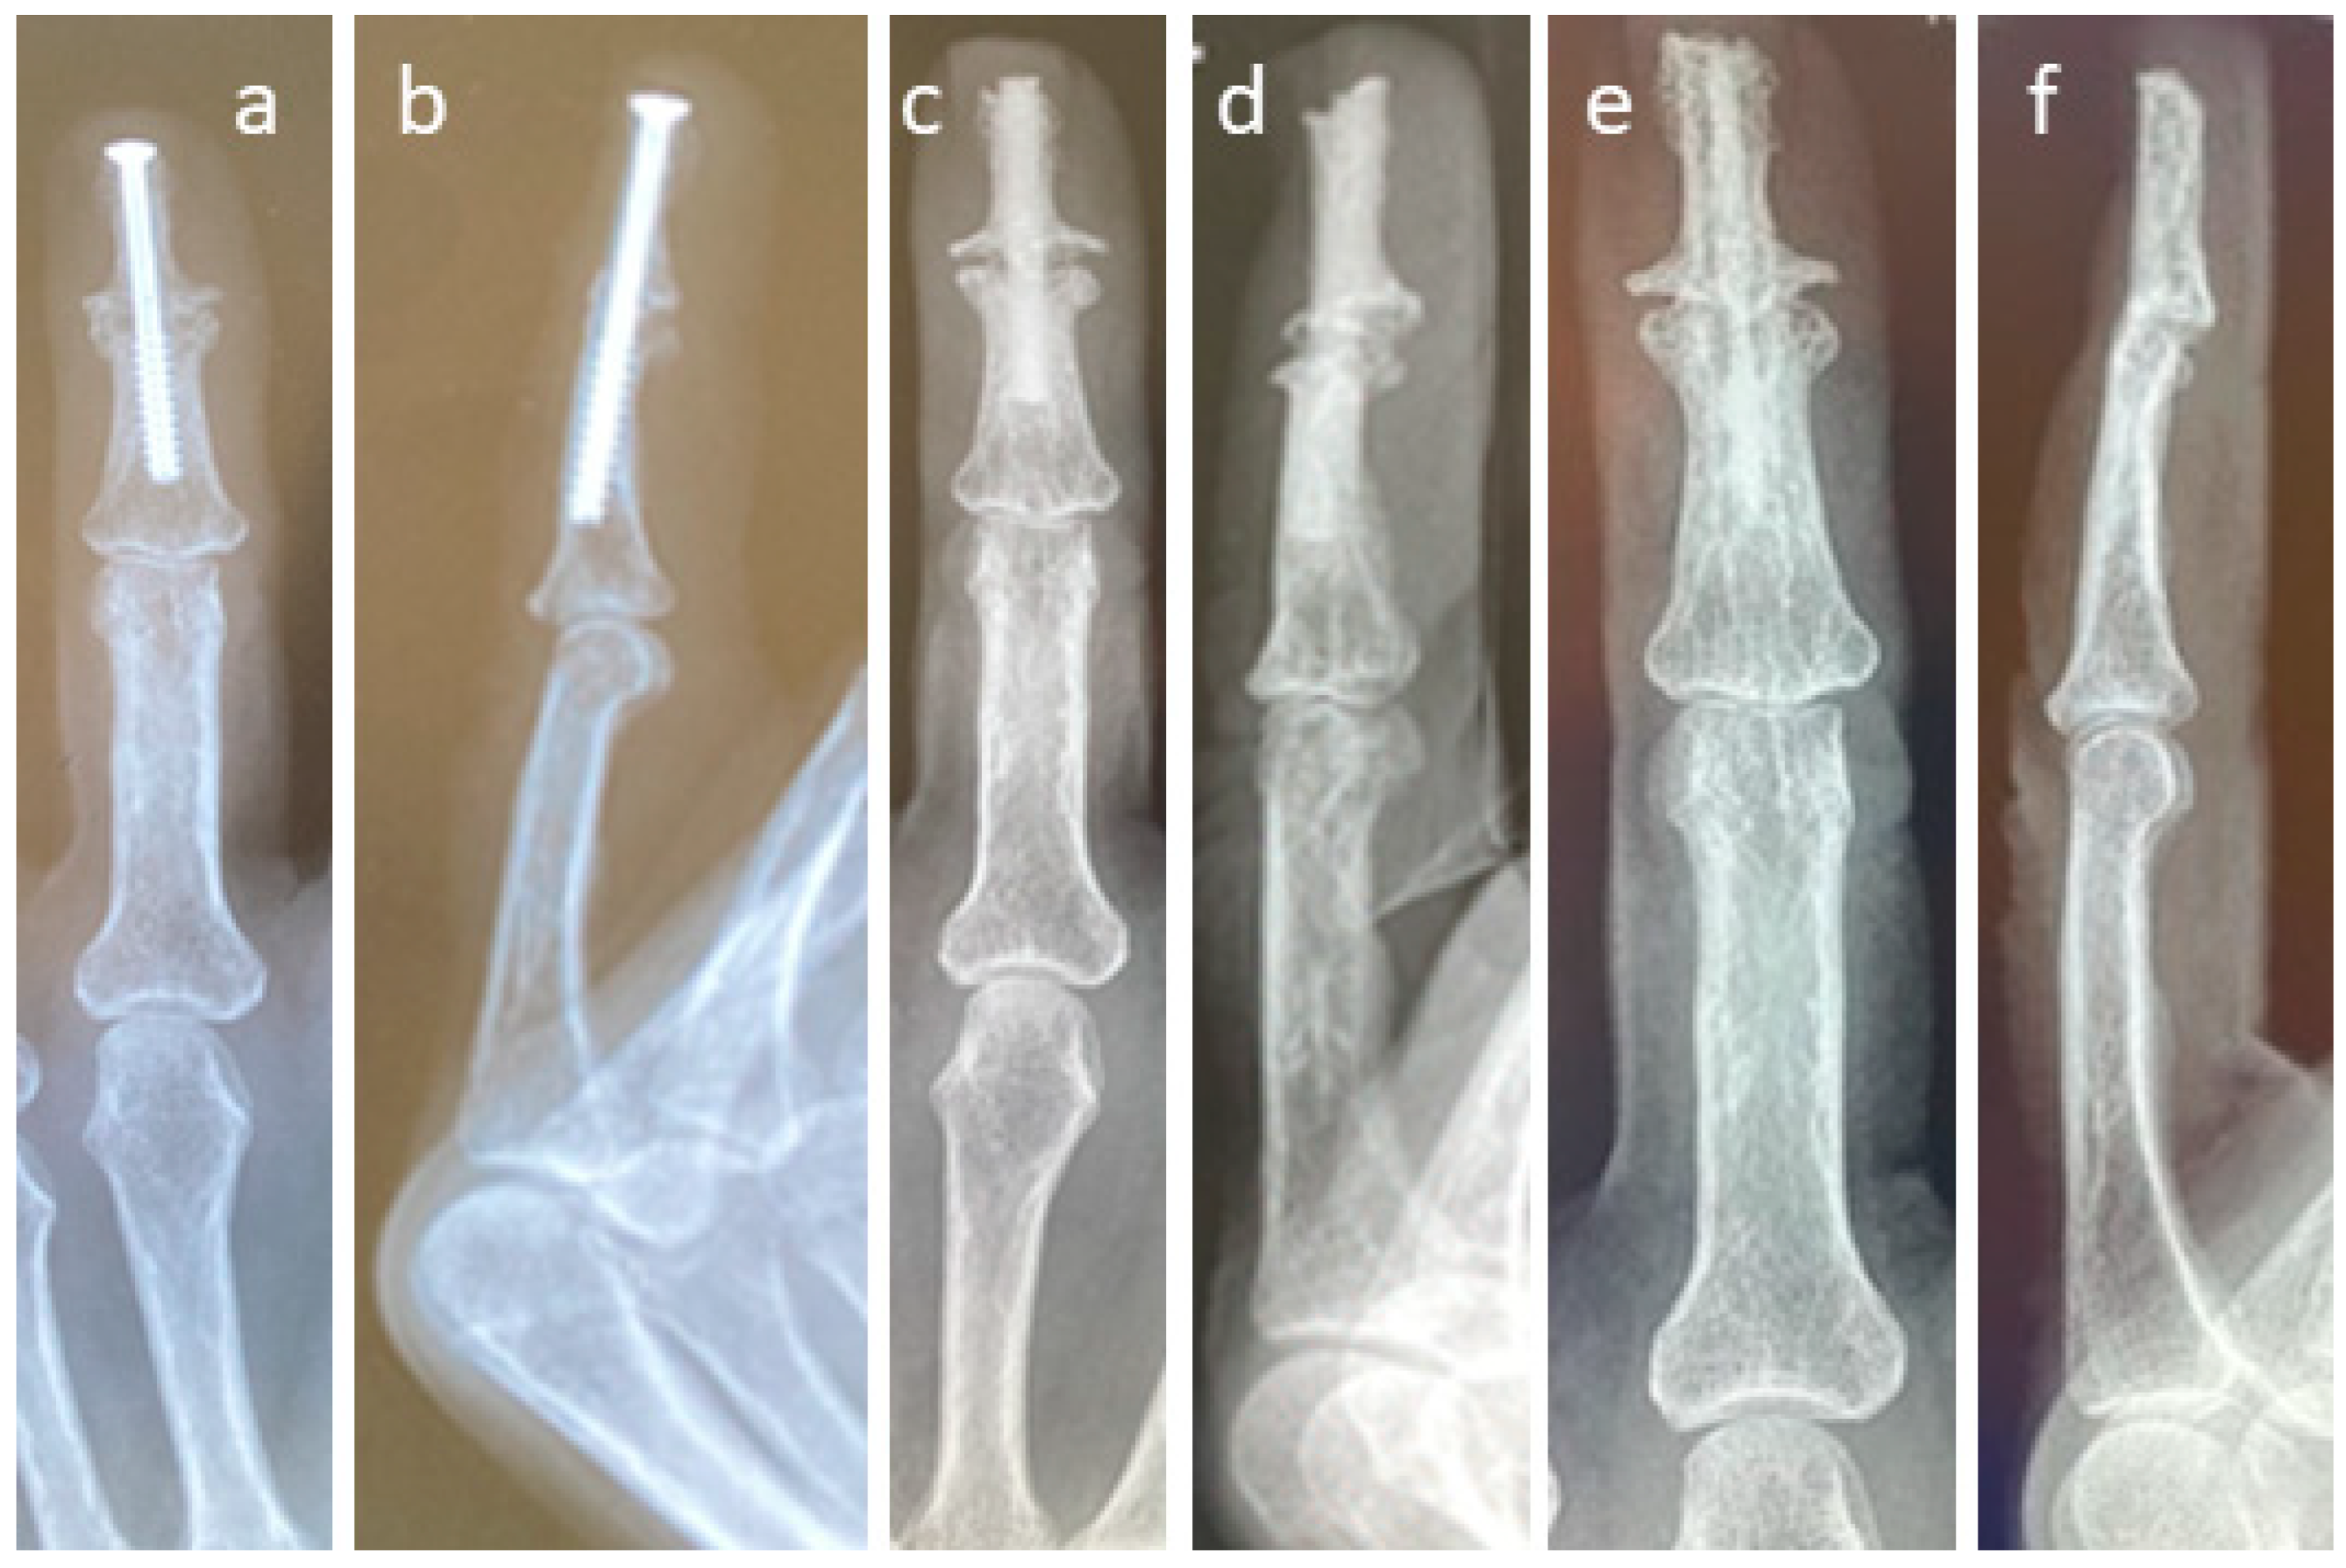

3.4. Selected Case Descriptions